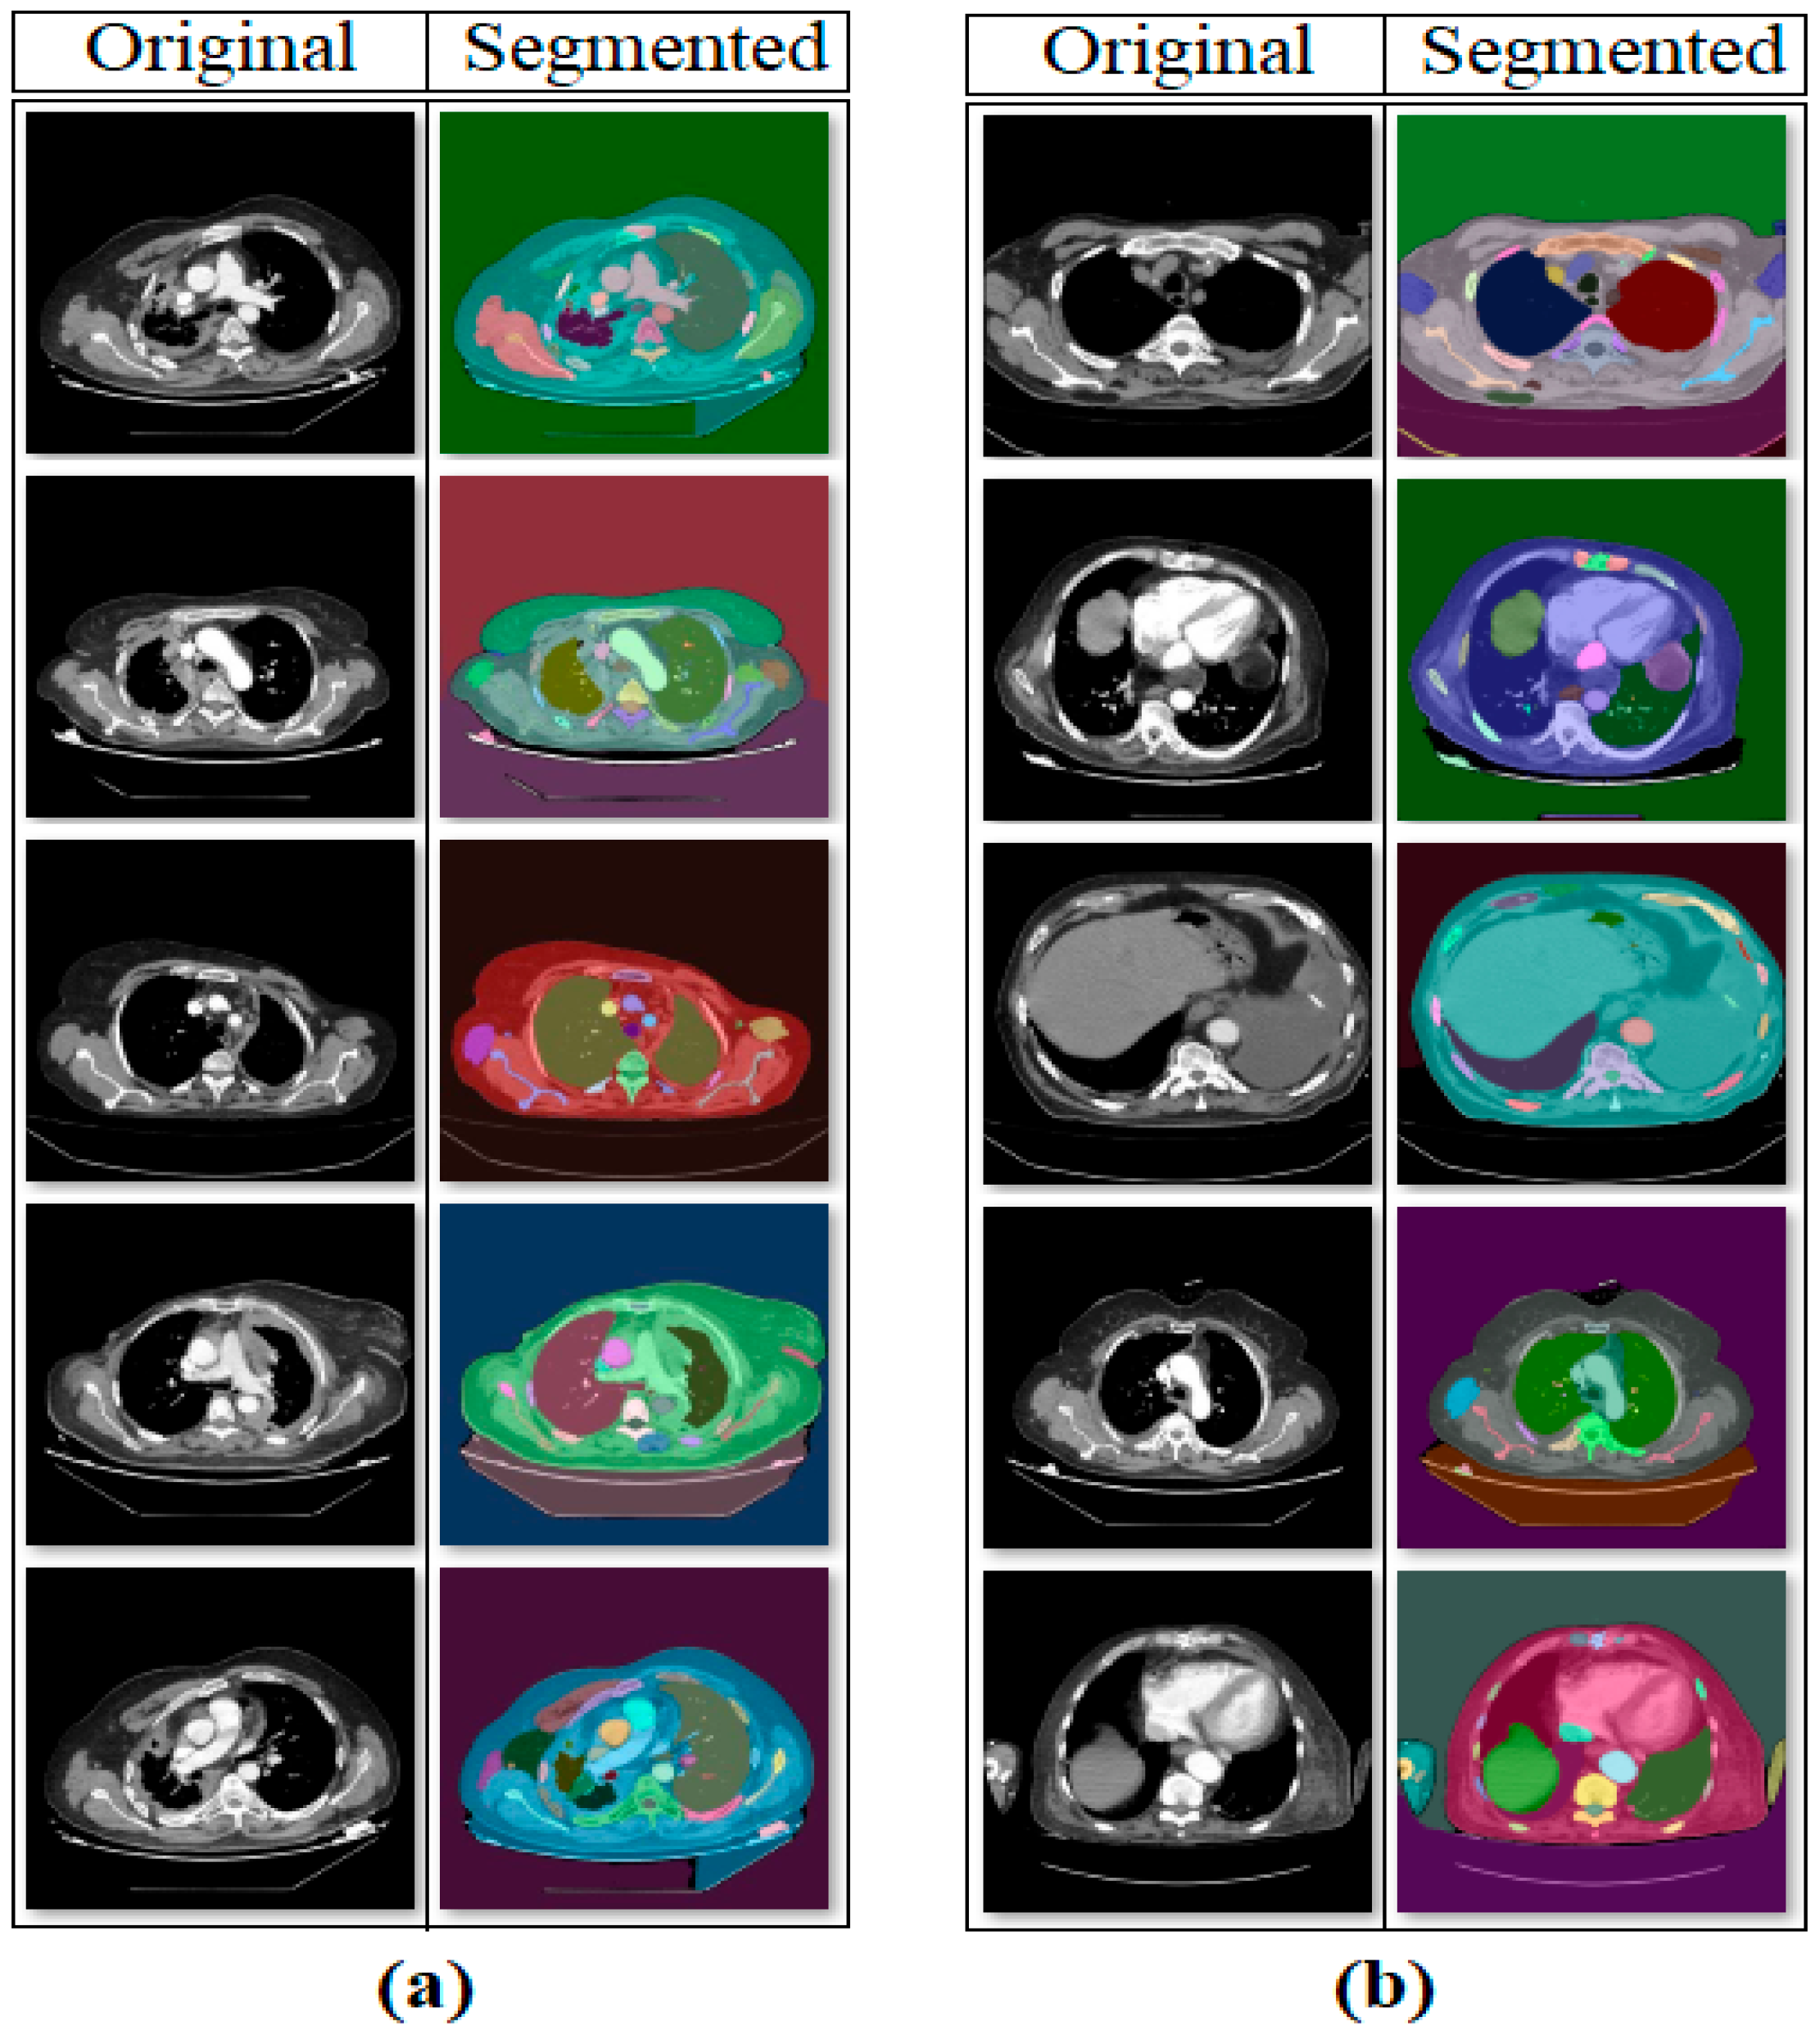

2.2. Segment Anything Model

- Meaningful regions were highlighted in CT images using the SAM method; deep learning models were enabled to focus on these regions and leave meaningless regions in the background.

- Numerical values in feature columns are represented as 2D images using generative techniques such as Decoder, GAN, and NeRV. This method allows approaches that operate on images to extract more diverse and rich numerical content from their architectural structures.